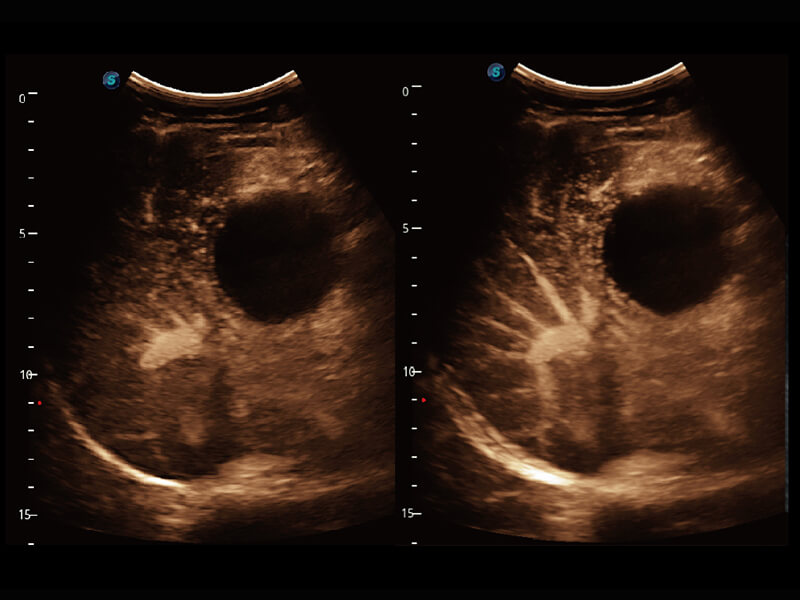

性能优异的硬件架构,极大提升超声系统的运行效率和数据处理能力。相比以往超声成像系统,Wis+平台为您带来极快的响应速度和成像帧频,提升检查流畅度。